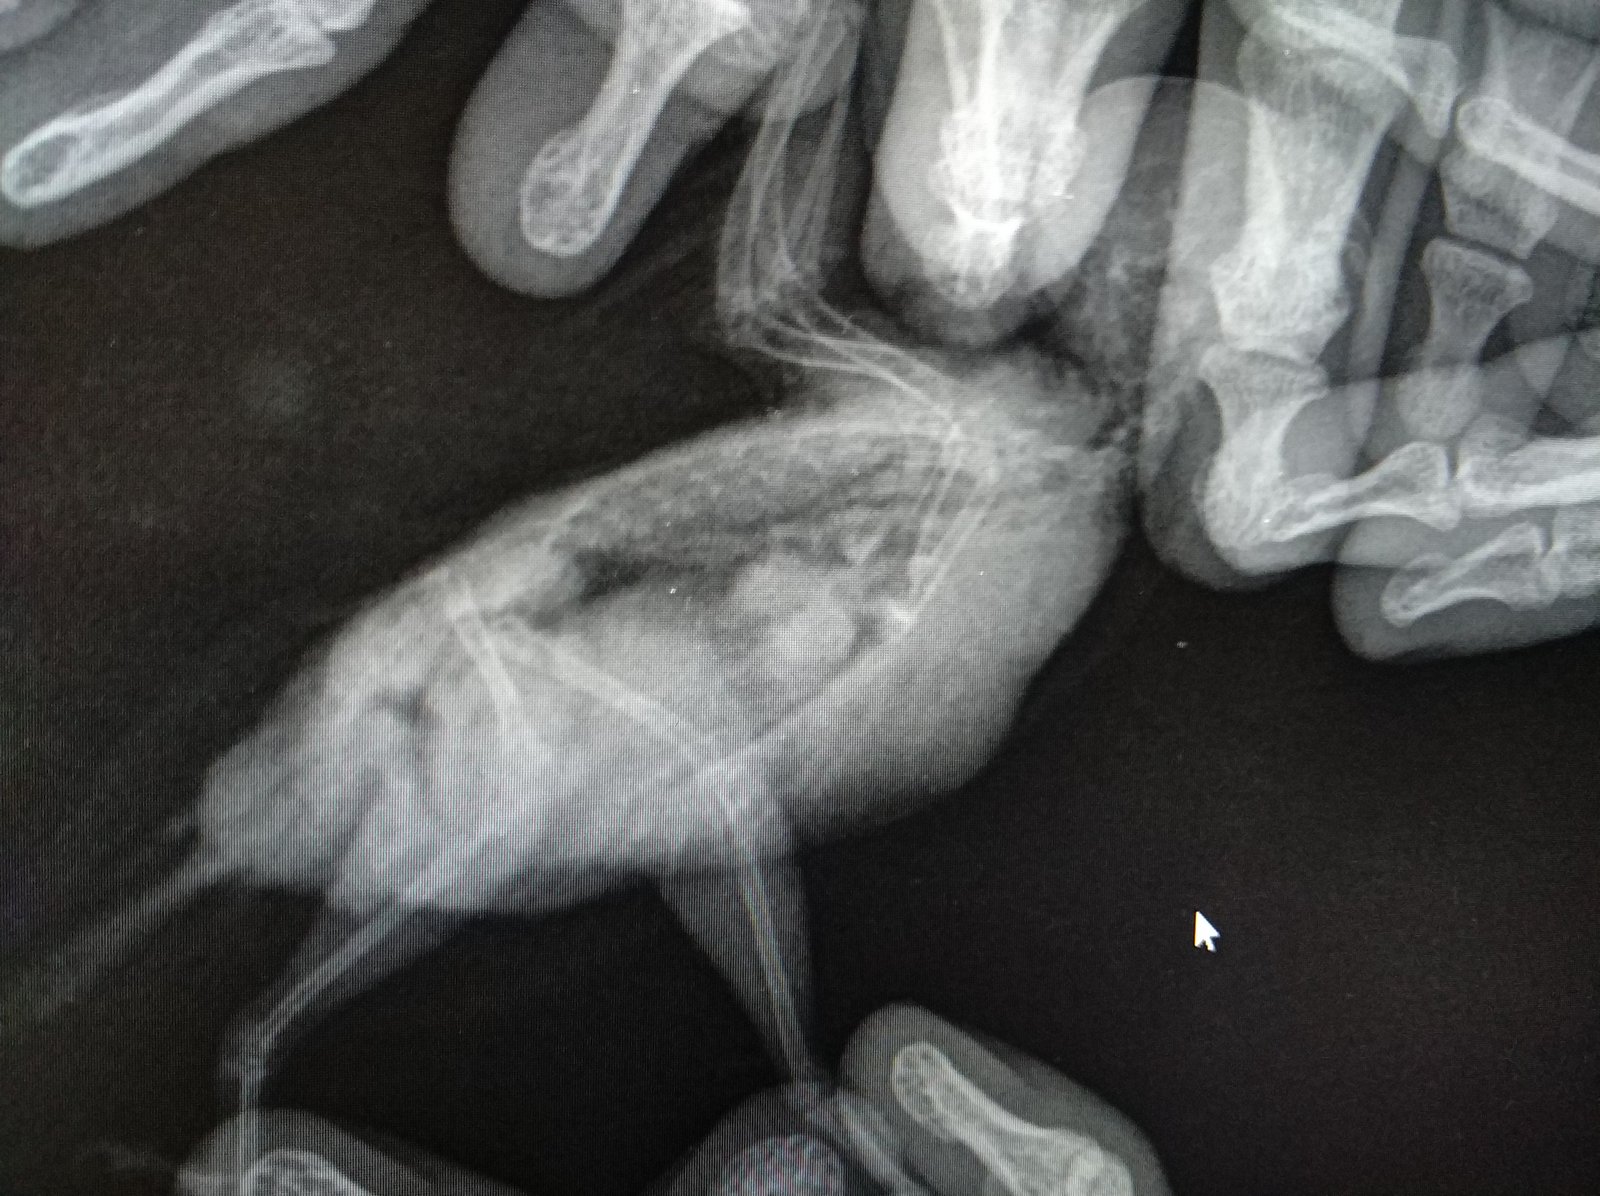

На следующий день поехали к орнитологу. Он не очень опытен (могу ошибаться, но он об этом говорил), а лучше я не нашел в городе. Он его пощупал, сделали рентген. Он сказал что с птицей все хорошо (за зрение ничего даже не сказал и не посмотрел), прописал следующее:

2. Гептрал\гепатовет (По рентгену сказал что печень плотно выглядит и надо давать это).